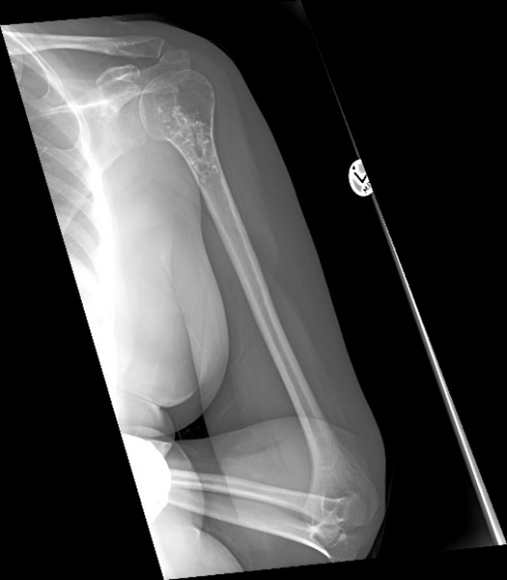

Osteosarcoma. There are many types of osteosarcoma but the most common is the classic intramedullary type which usually originates from the intramedullary cavity of the metaphyseal area of long bones. It is the most common type of bone sarcoma overall. It is most often found in teenagers and young adults. Any pathological fracture in a young person must be considered malignant until proven otherwise. The treatment of an osteosarcoma is classically neoadjuvant chemotherapy – surgery – adjuvant chemotherapy. The biopsy to diagnose bone sarcomas should be done by a sarcoma specialist to prevent difficulties with future surgery and spread of the tumour locally. The 5-year survival for patients with osteosarcoma is between 60% and 70%.